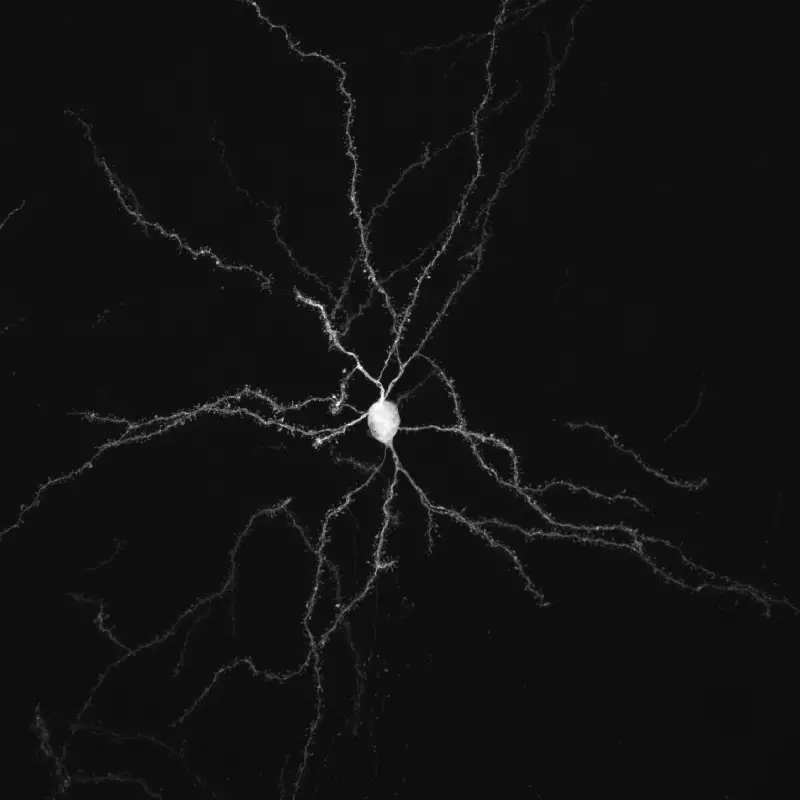

Notre principal intérêt de recherche porte sur la transmission synaptique, la neurodégénération et la neuroplasticité dans le cerveau adulte. La communication entre les neurones au niveau de leurs connexions, appelées synapses, est le substrat du traitement de l’information dans les réseaux qui sous-tendent les fonctions cérébrales. La transmission synaptique est un processus hautement dynamique et régulé, influencé par les cellules gliales, dont les anomalies sont associées à un certain nombre de maladies cérébrales (notion de synaptopathies). Neurodégénérescence est un processus pathologique qui déclenche le dysfonctionnement et la mort progressive des cellules nerveuses. La compréhension des mécanismes pathologiques qui déclenchent et entretiennent la neurodégénérescence (pathogenèse), de ses conséquences sur le fonctionnement des circuits et des mécanismes qui aident les neurones à gérer le stress cellulaire est essentielle pour le développement de traitements curatifs ou modificateurs de la maladie pour les troubles neurodégénératifs dévastateurs, tels que la maladie de Parkinson (MP). Neuroplasticité. désigne la capacité du système nerveux à s’adapter en réponse à l’expérience et aux stimulations internes ou externes en modifiant les interactions entre les cellules nerveuses, y compris les changements dans le nombre de synapses et l’efficacité/la force de la transmission synaptique (plasticité synaptique), ou en générant de nouvelles cellules nerveuses. Cette faculté n’est pas limitée au développement, mais se produit tout au long de la vie, bien qu’elle diminue avec le vieillissement. La neuroplasticité a notamment été impliquée dans les processus d’apprentissage et de mémoire. Elle se produit également dans des conditions pathologiques ou en réponse à des traitements chroniques. Ces changements adaptatifs peuvent représenter des mécanismes compensatoires contrecarrant les déficits déclenchés par le dysfonctionnement ou la mort neuronale, retardant l’apparition des symptômes, ou, au contraire, participer à ces déficits, voire les aggraver.

L’équipe étudie ces processus dans le contexte des fonctions et des pathologies liées aux ganglions de la base (BG), en particulier la MP, un trouble du mouvement caractérisé par la dégénérescence des neurones dopaminergiques du mésencéphale innervant le striatum, la principale station d’entrée des BG. Par le biais de collaborations, nos travaux abordent également des questions fondamentales et cliniquement pertinentes dans le contexte d’autres neuropathologies, notamment les troubles du spectre autistique (TSA), la maladie d’Alzheimer et la maladie de Charcot-Marie-Tooth.